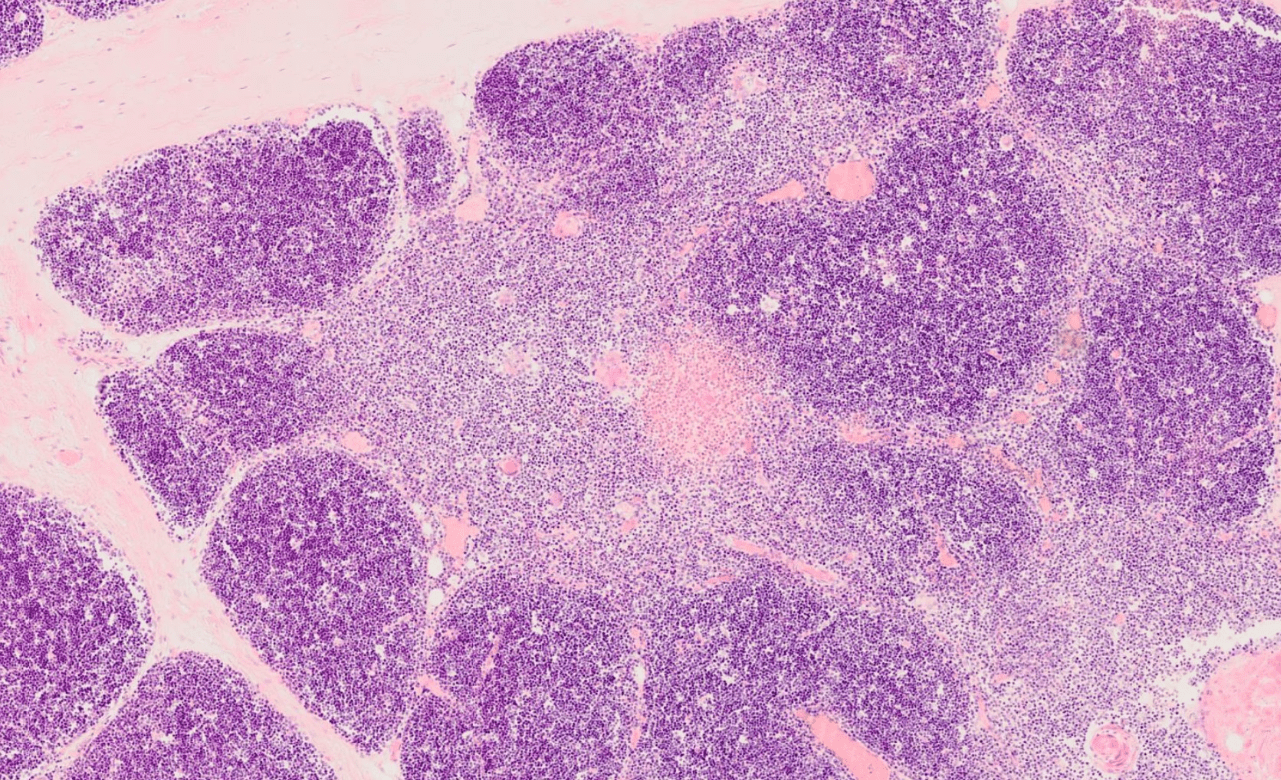

Organdiagnose

Thymus (juvenil)